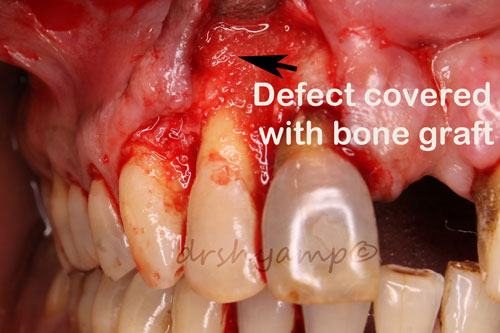

Periodontal flap surgery with bone grafting

Periodontal flap surgery with bone grafting

Periodontal flap surgery with bone grafting

Periodontal flap surgery with bone grafting

Periodontal flap surgery with bone grafting

Periodontal flap surgery with bone grafting

Periodontal flap surgery with bone grafting

Periodontal flap surgery with bone grafting

Periodontal flap surgery with bone grafting

Periodontal flap surgery with bone grafting

Periodontal flap surgery with bone grafting

Periodontal flap surgery with bone grafting

Periodontal flap surgery with bone grafting